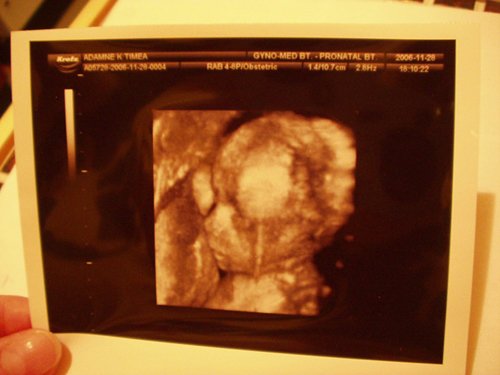

A 17. héten voltunk Pesten 3D-s uh-on Győrfi Mátyásnál a Praxisban. Azt mondta, minden rendben, szépen fejlett kisfiú:):):):)

Most 34 hetes vagyok, és kisfú lesz, Bence. Nem túl nagy baba, de azt mondják szép formás. A méretei inkább 32 hetesnek felelnek meg. Itt van pár kép róla 25+2 hetesen:) (a szeménél a köldökzsinór van! )